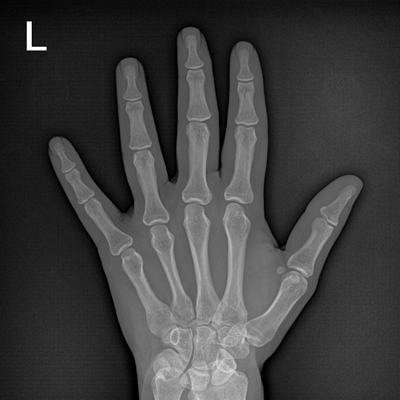

用于影像科、急診室、病房、ICU、手術(shù)室等多場(chǎng)景應(yīng)用。

● 數(shù)字化無線平板成像,操作簡(jiǎn)便,成像質(zhì)量高